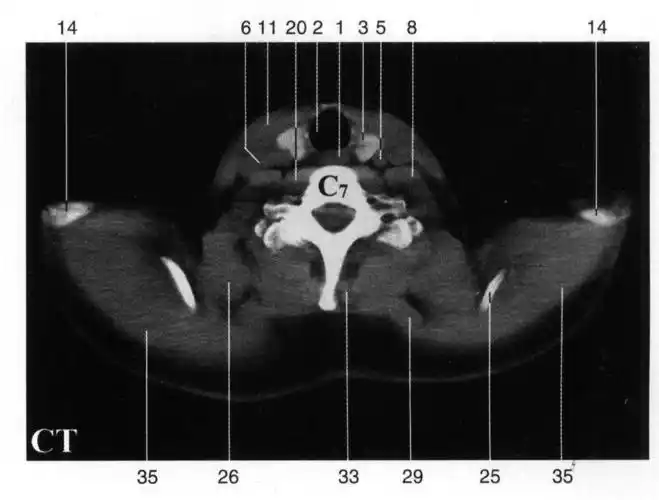

ht 1-断面解剖与mri ct ect对照-医学